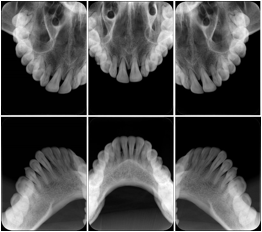

Cephalometric Series Structured Display

Figure OO-2. Cephalometric Series Structured Display

3. A dental provider wishes to capture a series of DICOM IO images for the patient’s dentition. The tooth morphology, teeth are divided into molars, premolars, canines and incisors, and a number of images for each jaw. The anatomic information was captured utilizing the triplet of schema. This standard code sequence is based on ISO 3950-2010, Dentistry - Designation system for teeth and areas of the oral cavity.

Every IO image should have anatomic information either through the primary or modifier sequence.

In most standard cases, images are oriented in structured layouts. These structured displays are useful to be shared between providers for reference purposes.

Table OO.1.1-1 shows structured display standard templates, where Viewset ID is based on the Japanese Society for Oral and Maxillofacial Radiology (JSOMR) classification provided by JIRA (Japan Medical Imaging and Radiological Systems Industries Association, www.jira-net.or.jp). Expected or typical teeth to be imaged location, region and designation codes are based on ISO 3950-2010, Dentistry - Designation system for teeth and areas of the oral cavity. For all the hanging protocols listed in OO.1.1-1, the value to use for Hanging Protocol Creator (0072,0008) is "JSOMR" and the value to use for Hanging Protocol Name (0072,0002) does not include "JSOMR" (e.g., "DL-S001A", not "JSOMR DL-S001A").